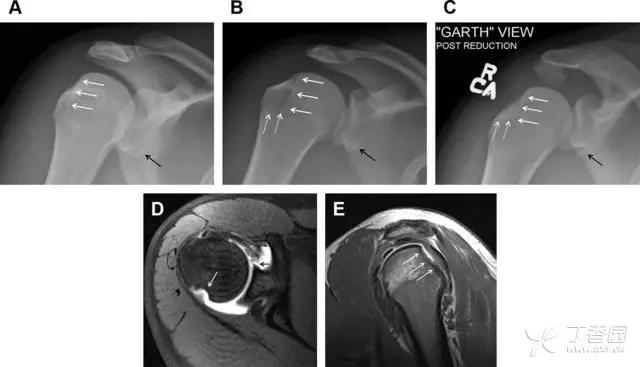

28 骨折伴盂肱关节不稳

肩关节是最容易脱位的关节之一,肩关节脱位常伴随其它结构的损伤,如血管神经损伤、肩袖损伤、盂唇损伤、Bankart 损伤等。脱位本身诊断往往是明确的,容易被忽略的是其继发的伴随损伤。

需要仔细评估肱骨头、大结节、关节盂边缘、肩峰、喙突等结构。典型的 X 线投射角度包括:内旋位前后位片、外旋位前后位片(Grashey 位)、侧位(肩胛骨 Y 位)、腋位片以及改良腋位片。

图 6 肩关节前脱位伴有 Hill–Sachs 和 Bankart 损伤:(A~C)肱骨头后外侧撞击骨折,白色箭头所示为骨折的内侧边界;(A)内旋位前后位片,(B)「V」形压缩骨折的下边界(虚线短箭头),(C)Garth 位(轴向投影)示 Hill–Sachs 损伤(虚线和实线折箭头),特别是对骨性 Bankart 损伤的诊断有帮助。(D、E)MRI 进一步证实了损伤

图 7 肩关节后脱位伴有反 Hill–Sachs 损伤。(A)外旋位前后位片可见一硬化带(黑箭头),此「凹槽征」与肱骨头关节面平行;(B)腋位片进一步证实了骨折的存在